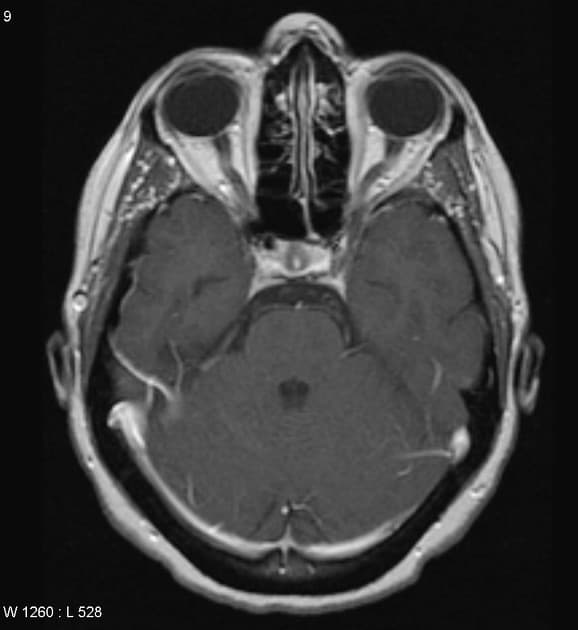

- Khối liên tục với cuống yên, làm giãn cuống này cả phía trên và phía dưới.

- Phù hợp với kiểu tăng quang đặc trưng và nằm trong cuống yên (infundibulum).

- Khối phù hợp với kiểu tăng quang đặc trưng và nằm trong cuống yên (infundibulum).

- Khối liên tục với cuống yên, làm giãn cuống cả phía trên và phía dưới.

- "Đặc điểm hình ảnh gồm khối u ranh giới rõ, tăng quang mạnh, liên tục với và làm giãn cuống yên."

U Pituicytoma là một loại khối u thần kinh đệm lành tính, phát triển chậm và hiếm gặp, xuất phát từ các tế bào pituicyte ở thùy sau tuyến yên hoặc cuống yên. Khối u thường biểu hiện như một tổn thương ranh giới rõ, tăng quang mạnh và liên tục với, đồng thời làm giãn cuống yên. Trên cộng hưởng từ (MRI), khối u thường có tín hiệu đẳng trên hình ảnh T1 và tăng quang đồng nhất sau khi tiêm thuốc cản quang. Việc không có dấu hiệu ác tính, không bệnh toàn thân và tổn thương ổn định dài hạn trên hình ảnh học làm tăng khả năng chẩn đoán u Pituicytoma, ngay cả khi chưa xác định bằng mô bệnh học. Các chẩn đoán phân biệt bao gồm u tuyến yên có liên quan đến cuống yên, u màng não và bệnh tổ chức bào Langerhans, những bệnh này có thể có hình ảnh tương tự. Tuy nhiên, vị trí đặc hiệu trong cuống yên và sự liên tục với cuống làm nghiêng về chẩn đoán u Pituicytoma. Điều trị thường mang tính theo dõi bảo tồn, đặc biệt ở bệnh nhân không có triệu chứng.